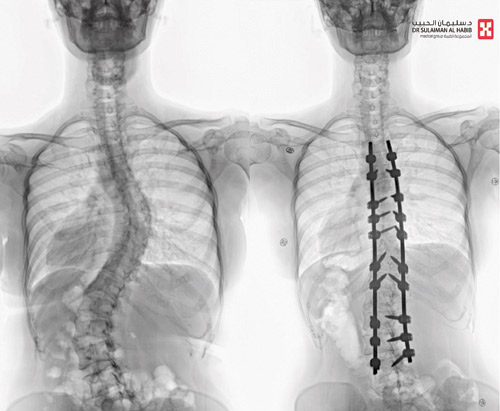

وقال د. خليفة إن المريضة راجعت المستشفى وهي تشتكي من انحناء جانبي للعمود الفقري منذ صغرها، بدأت مؤخراً تعاني من آلام بالظهر، إضافة إلى صعوبة في ممارسة الحياة الطبيعية، وقد أدت هذه الأعراض إلى تغيير نمط حياتها والحد من حركتها، وفور وصولها إلى المستشفى أجريت لها التحاليل والفحوصات الطبية الدقيقة، التي بينت إصابتها بحالة انحراف «جنف» مضاعف بدرجة 60 للفقرات الصدرية، ودرجة 50 للفقرات القطنية ودرس الفريق الطبي الحالة على ضوء نتائج الفحوصات والتحاليل، وخلص إلى ضرورة التدخل الجراحي لعلاج العيوب، والحد من المضاعفات، وبعد اتخاذ كافة التدابير الطبية اللازمة لمثل هذه الحالات المعقدة، أخضعت الشابة لعملية جراحية، تم فيها تقويم العمود الفقري بعدد «20» من البراغي والقضبان المعدنية والطعوم العظمية الصناعية وتثبيت ودمج الفقرات، واستخدمت في العملية التي استمرت لـ»4» ساعات.

وبعد العملية نقلت المريضة إلى جناح التنويم، وبدأت حالتها في التحسن باطراد واستطاعت المشي بتوازن بعد أقل من «24» ساعة من العملية بمساعدة فريق العلاج الطبيعي المتمرس، واستعادت قدرتها على الاستلقاء والنوم على ظهرها، فضلاً عن القوام والمظهر الطبيعي، بعد تعديل وضعية الحوض والكتف، كما أن طولها مع النجاح الكبير للتعديل زاد بحدود «3» سم، وخرجت من المستشفى وهي بصحة جيدة، وتوقع أن تستعيد كامل عافيتها سريعاً مع الإنتهاء من برنامج العلاج الطبيعي.